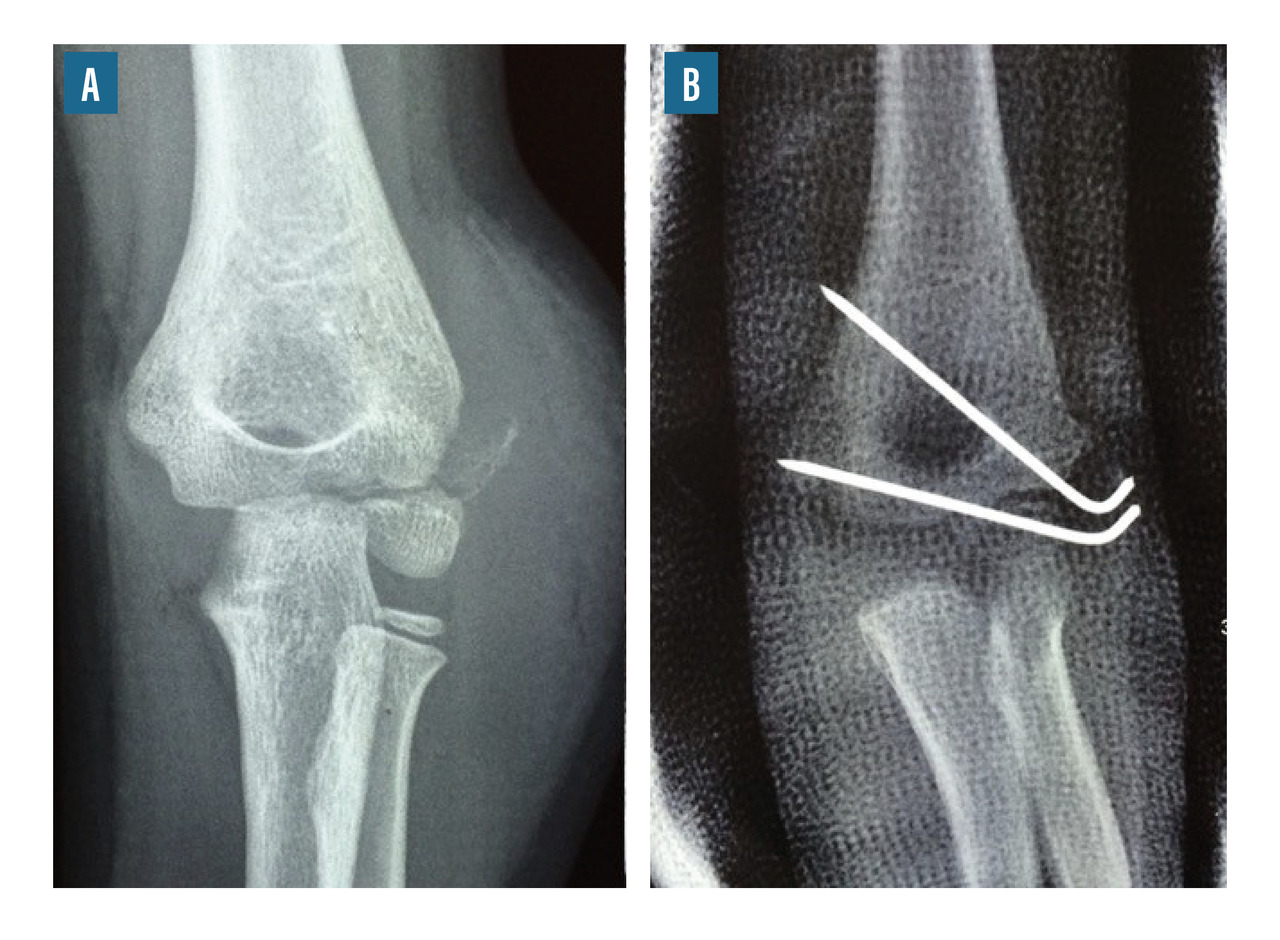

• le brochage direct (fig. 8) ;

Le traitement chirurgical peut nécessiter un abord chirurgical, notamment dans les cas de fractures articulaires (fracture du condyle latéral, fractures intercondyliennes). Dans les autres cas, il s’agit habituellement de réductions orthopédiques maintenues par des broches ou un simple plâtre.